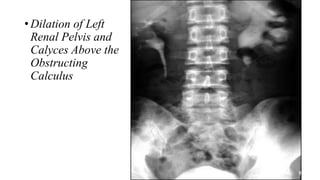

Renal collecting

system and ureters

Crossed Renal

Ectopia on the

Left Kidney and

Absent Right

Kidney.

Renal collecting system andureters Crossed Renal Ectopia on the Left Kidney and Absent Right Kidney.